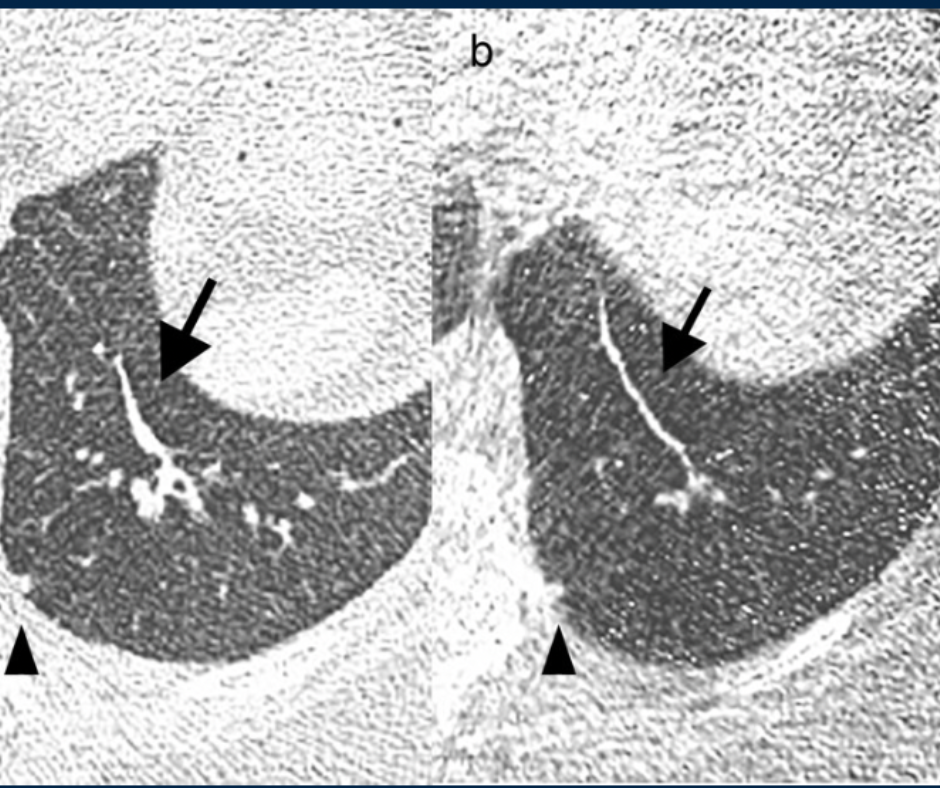

However, the researchers noted that agreement between ULDCT and LDCT ranged between 60 to 80 percent for septal thickening, pleural effusion, and consolidation. They also noted poor agreement (37 percent) for ground glass opacification (GGO) lesions.

While the researchers noted the use of ULDCT could reduce effective radiation dosing to a third of that used for LDCT, they said the significant potential for missing other lung cancers such as lepidic adenocarcinoma outweigh the benefits of reduced radiation dosing.

“Despite the exciting agreement for some pulmonary findings, these results question whether using an ULDCT protocol for (lung cancer screening) would be adequate as many subsolid or GGO lesions could be missed,” wrote Matheus Zanon, MD, MSc, who is affiliated with the Department of Radiology at Pontificia Universidade Catolica do Rio Grande do Sul in Porto Alegre, Brazil, and colleagues.